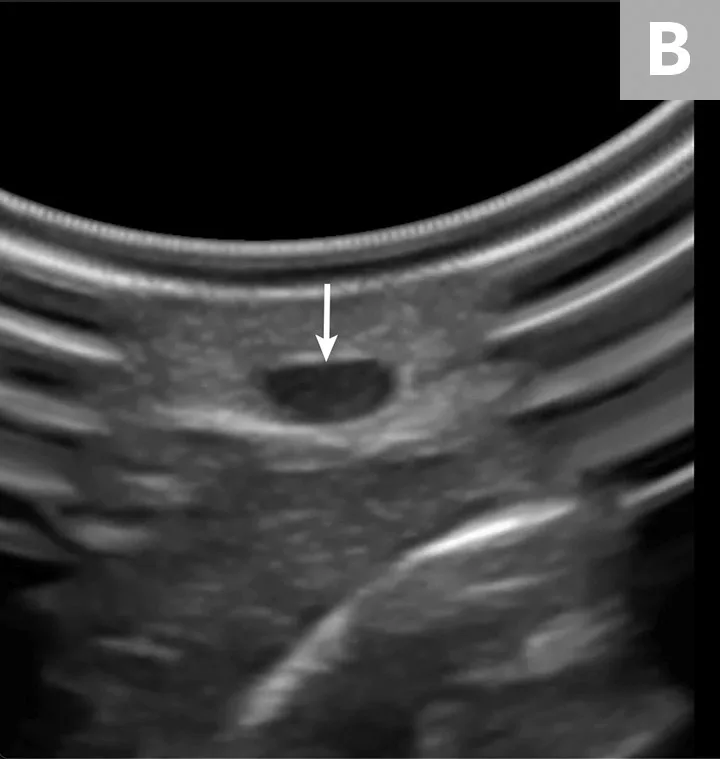

Insert the catheter needle and stylet into the skin at a 30- to 45-degree angle, just distal to the probe (A). Identify the needle tip as a white dot (B, arrow) on the display between the skin and the vessel, and stop advancing.

Ultrasound probe held over limb of pet and ultrasound image with arrow pointing to needle seen within blood vessel.